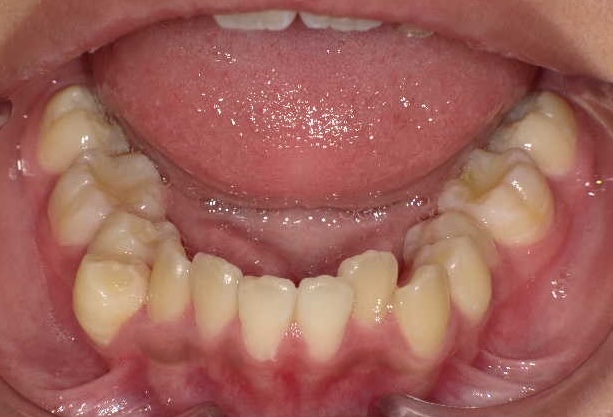

症例1-②

そして、永久歯がすべて生えそろって症例1-②の写真のようになります。上は、軽度の八重歯です。この程度の八重歯は永久歯を抜くことなく治療可能ですが、問題は右下の4番がスペースがまったく無いということです。ここで、一般的な矯正では、右下4番の小臼歯の抜歯と、それに伴う、その他3本の小臼歯の、計4本の永久歯の抜歯を提案されるでしょう。